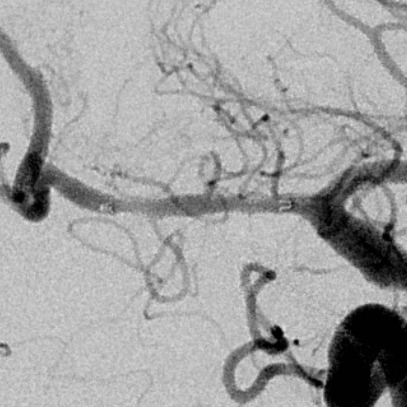

右侧MCA长节段血管变细狭长

长节段MCA血管狭长变细,尤以近端为重

乍一看血管似乎还可以

重建的形态

血管形态

放大后仔细观看,近端有局限性血管变细,并见双腔征

另外时相远端也隐约局限性变细